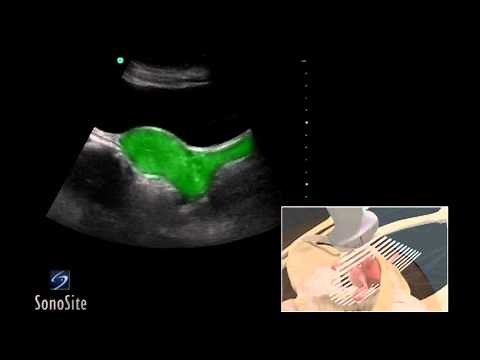

Ultrasound - Pelvic Ultrasound

Ultrasound - Female Pelvis

Ultrasound - Female Abdomen